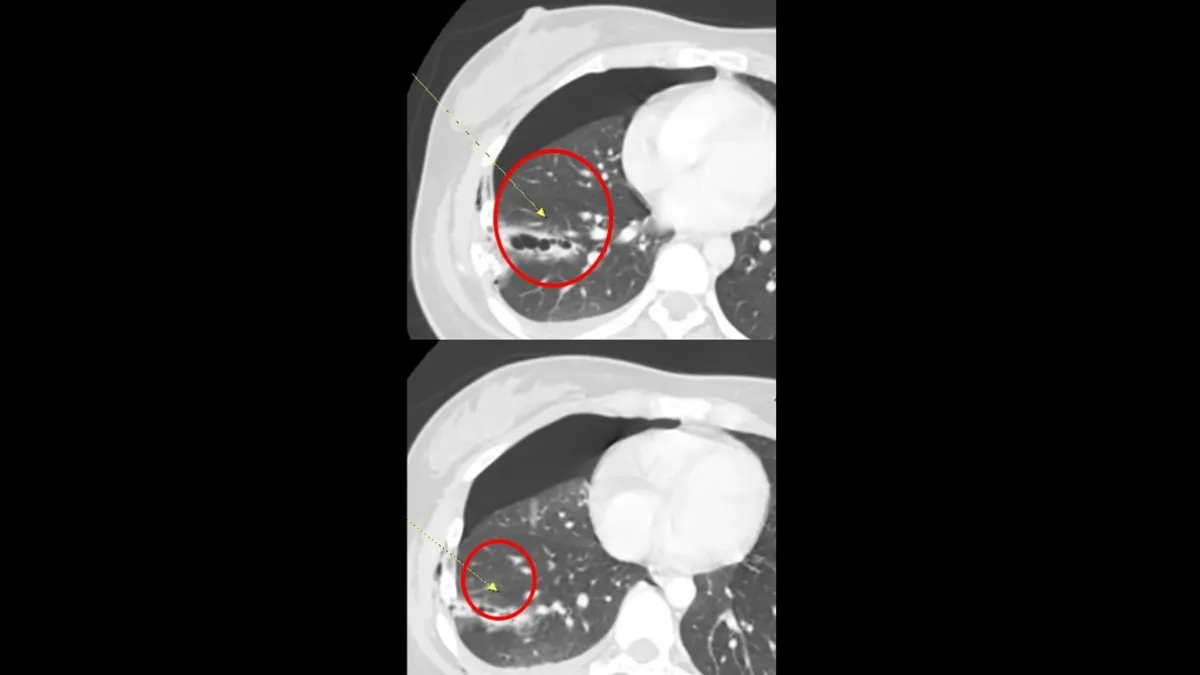

直到轉送桃園醫院急診,經該院神經內科趙化全醫師安排電腦斷層、肌電圖及腰椎穿刺等精密檢查後,才終於確診罹患「急性發炎性脫鞘多發神經病變」,也就是俗稱的格林-巴利症候群。